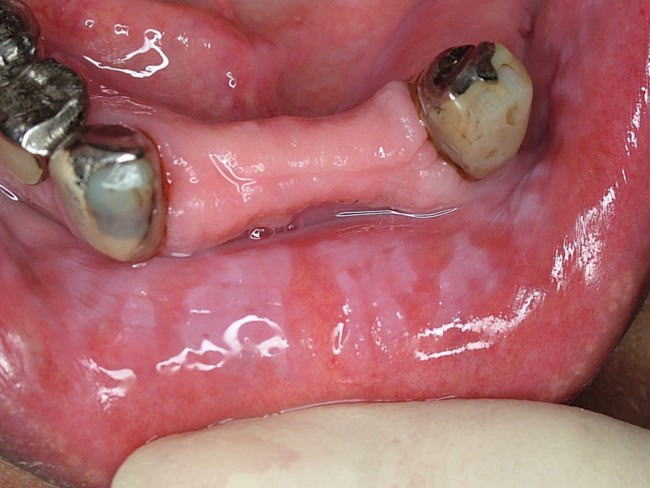

頬粘膜をはじめ口唇、舌、歯肉、口腔底粘膜などに発現する”摩擦によって除去できない”白斑病変。下の写真は口唇に発現した白板症(同一写真)です。口腔粘膜疾患としては比較的頻度が高く、単発で生じることも、また写真のように広範囲に生じることもあります。表面は粗いもの、丘陵上のもの、乳頭状のもの、また境界が限局性のもの、びまん性のものなど様々な病態を示します。状態によっては前癌病変としての性格を持つものもあります。

疼痛などの自覚症状は少ないのが普通です。

治療は原因除去(不適合な補綴物の刺激によって生じたものなど)、切除、レーザー照射などがありますが、原因や病態によって多様です。

鑑別診断を要するものとしては、扁平苔癬やカンジダ症などがあります。